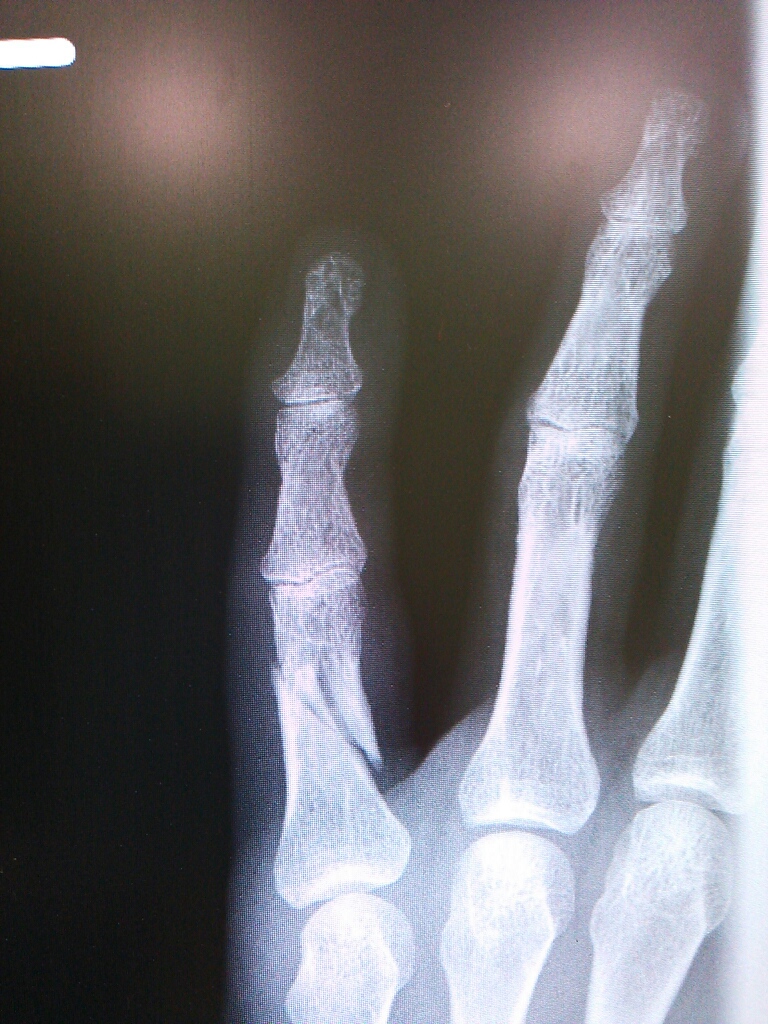

金曜にレントゲン撮ったけどあんまり変わってない…。

まだくっついてないし痛いんですけど…。